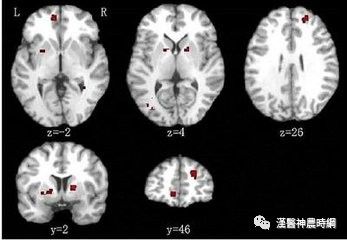

神经解剖和神经影像学研究显示,患者颞叶、额叶及边缘系统存在脑组织萎缩,脑室扩大和沟回增宽。母孕期病毒感染,围产期并发症,幼年的不良应激和躯体疾病,与神经系统发育缺陷有关,在精神分裂症发病中有一定影响。